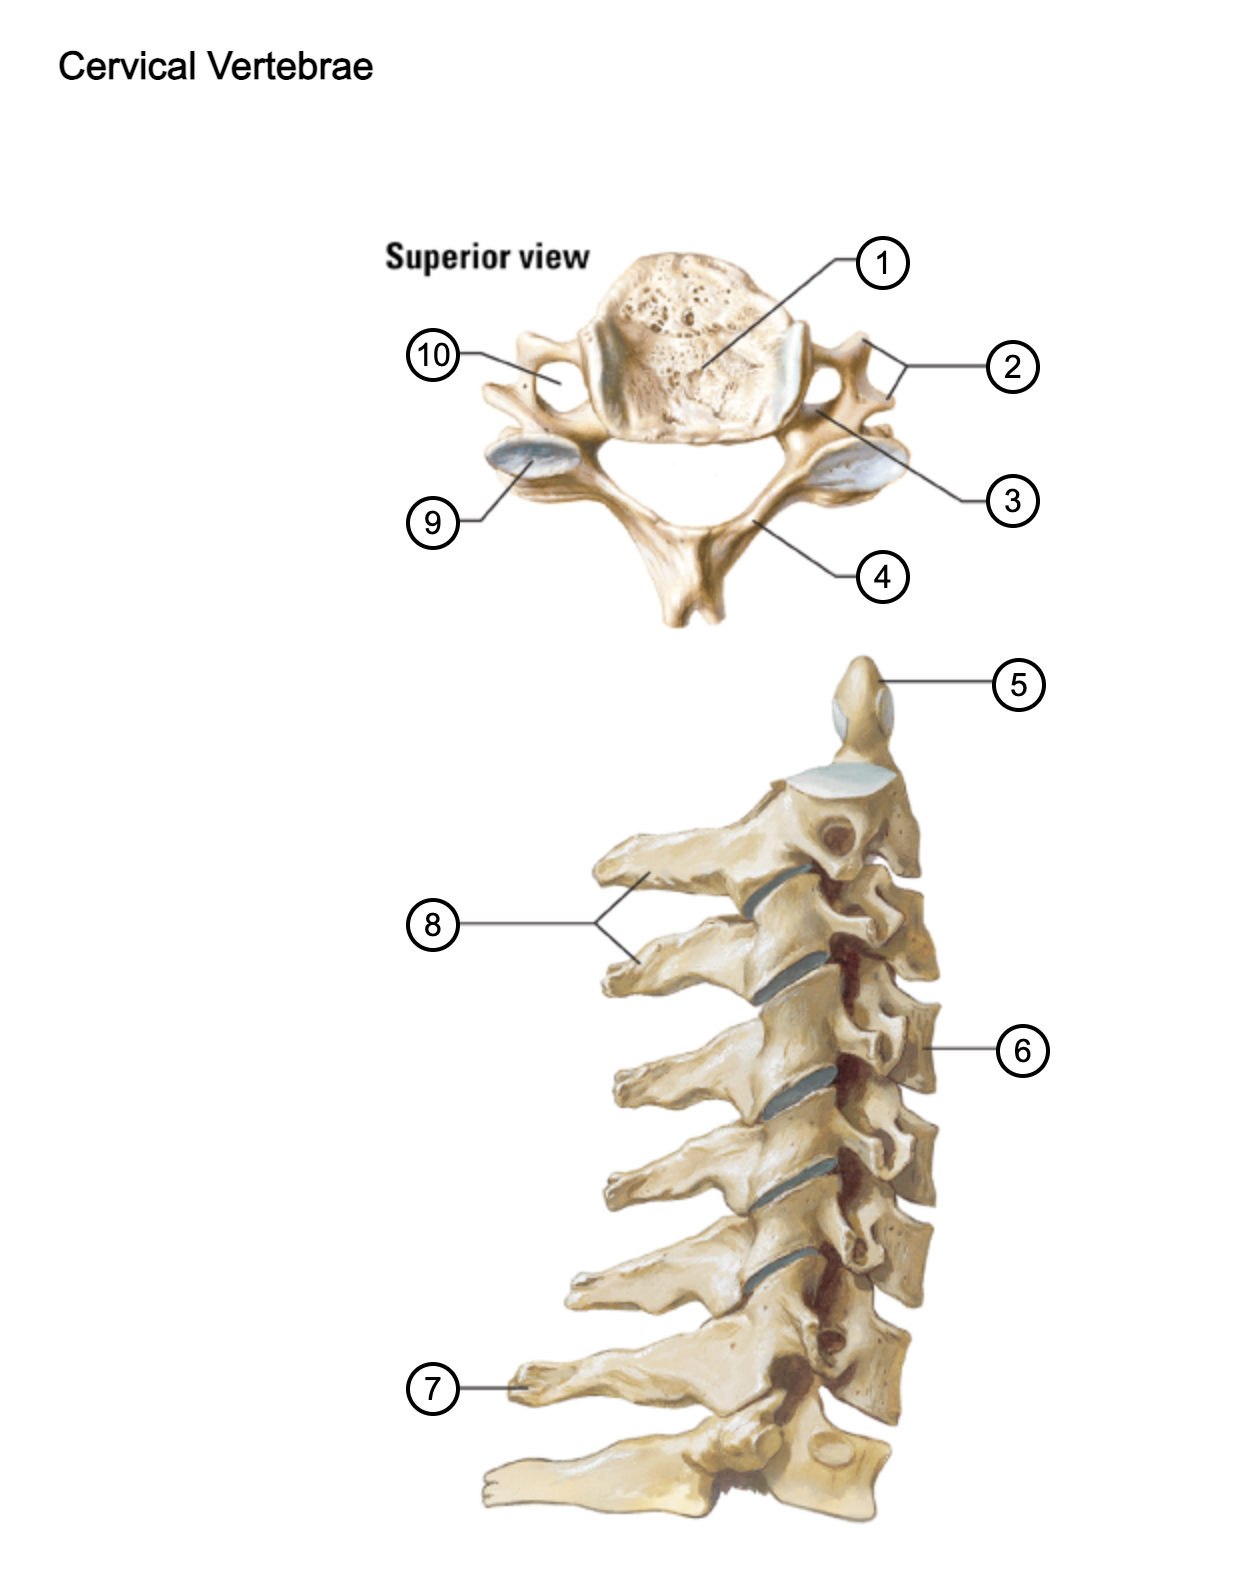

1

vertebral body

2

transverse process

3

pedicle

4

lamina

5

dens axis

6

vertebral body of C4

7

spinous process C7 (vertebra prominens)

8

spinous processes (C2 and C3)

9

superior articular process of C4

10

transverse foramen